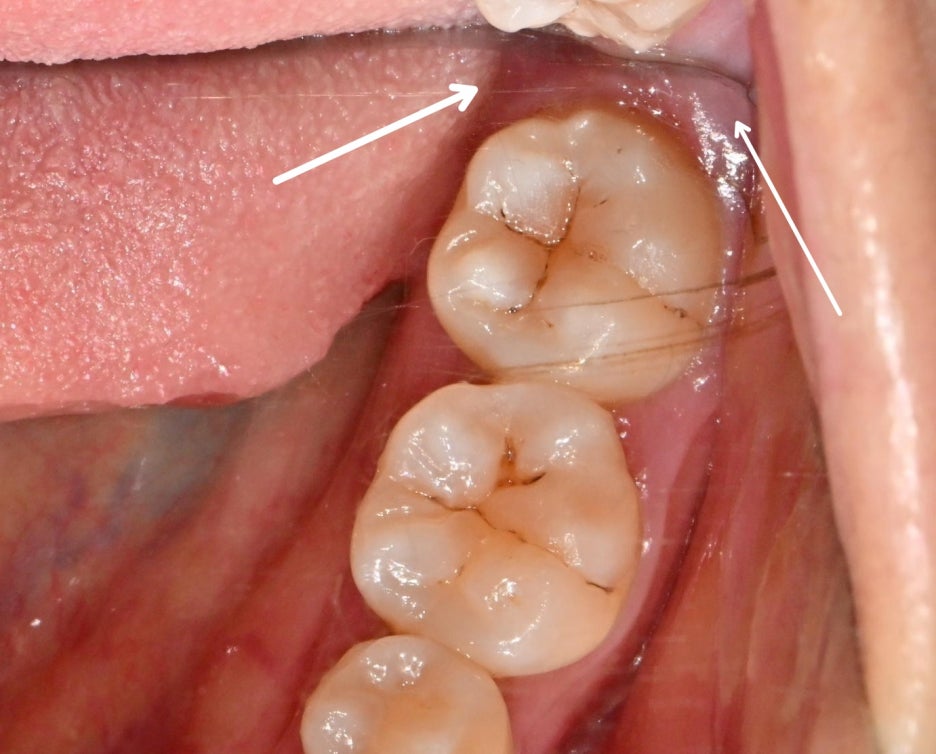

특히 어금니 사이에는

좁고 깊은 공간이 형성되면서

음식 찌꺼기가 쉽게 끼는 반면에

칫솔질로 청소하기 어렵고

거울로는 정확하게 확인할 수 없어

위생 관리의 사각지대가 될 수 있습니다.

치아 곳곳에는 치석이 붙어 있고

치은 연하에도 치석이 부착된 것으로 봐서

치주염을 짐작해 볼 수 있는 환경이며,